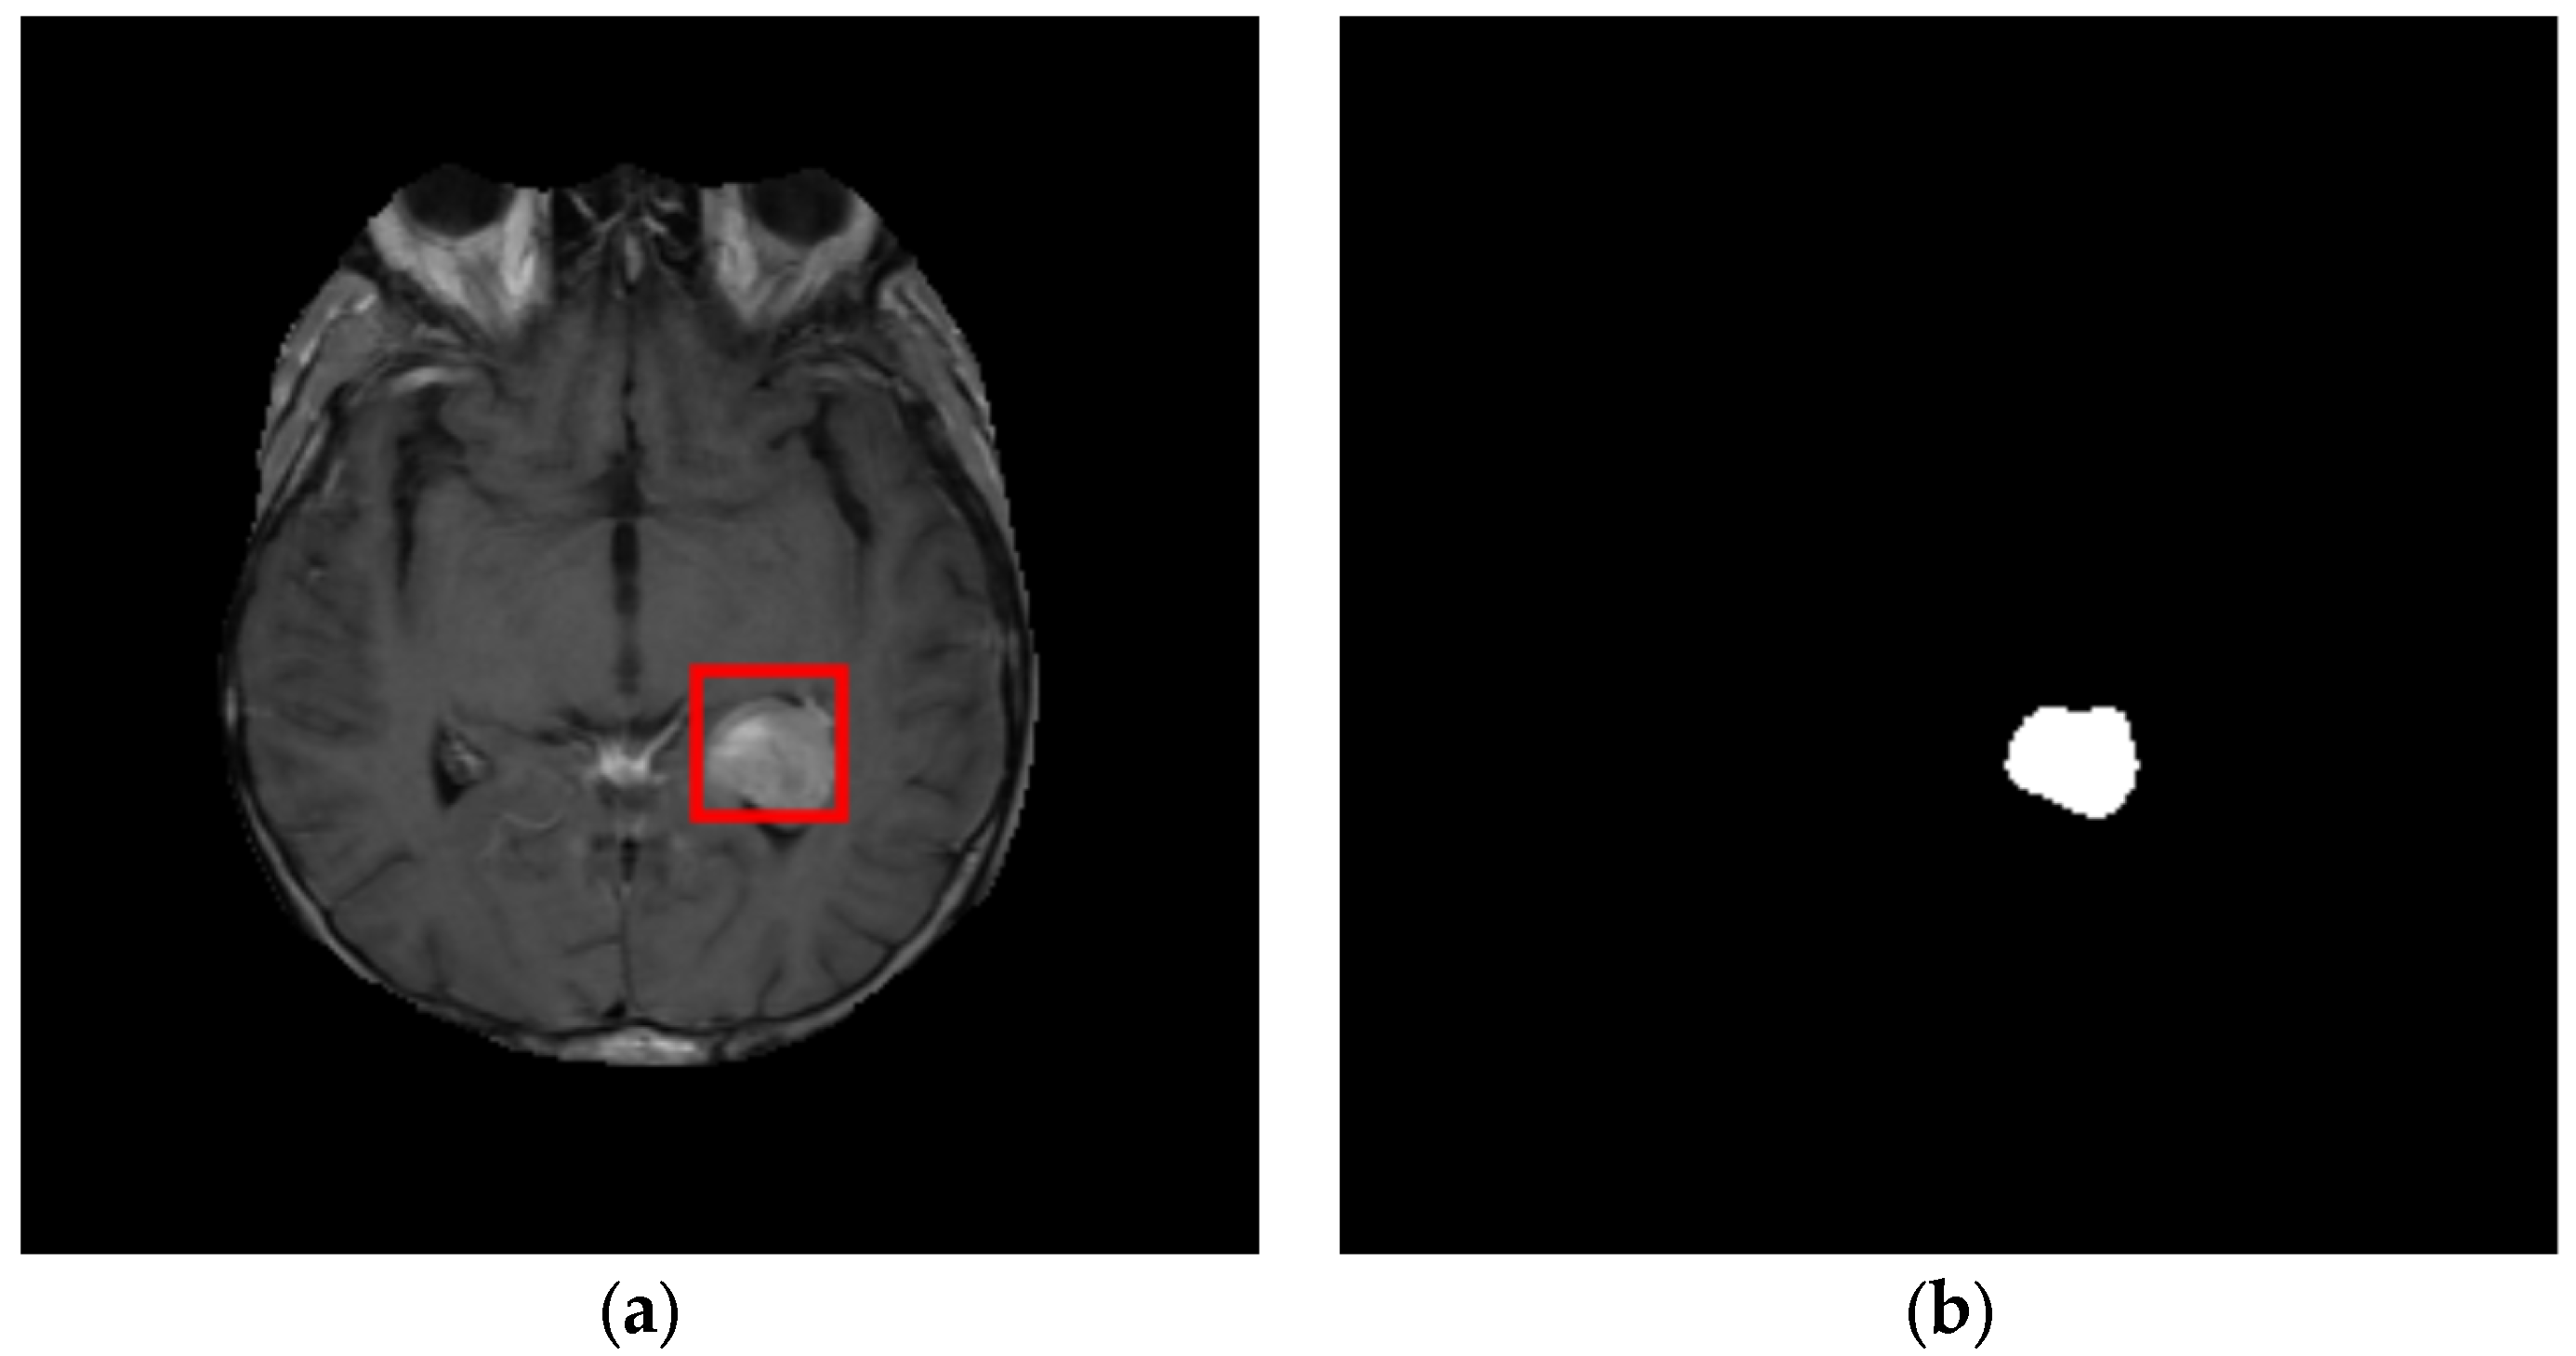

3.2. ROI Detection

3.3. Tumor Segmentation

4.1.2. Experiments

- Experiment #1